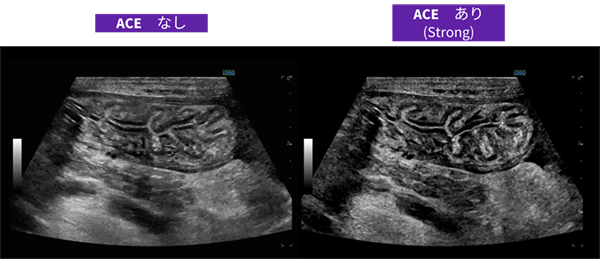

● CPU/GPUハードウェアを基盤に膨大なデータをリアルタイム再構成,全ピクセルを最適化するcSound Imageformerや位相のゆがみを判断する高画質化技術ACEを搭載することで,画像の精度の向上を実現。

フラグシップモデルのLOGIQ E10シリーズと同じcSound Imageformerが搭載されており,近位部から深部に至るまで均一なイメージを提供するために全視野・全深度フルフォーカスを実現している。位相のゆがみを判断する高画質化技術ACEの搭載によりさらに深部まで高画質に描出することができ,体格のよい被験者においても明瞭な画像を実現できるようになった。